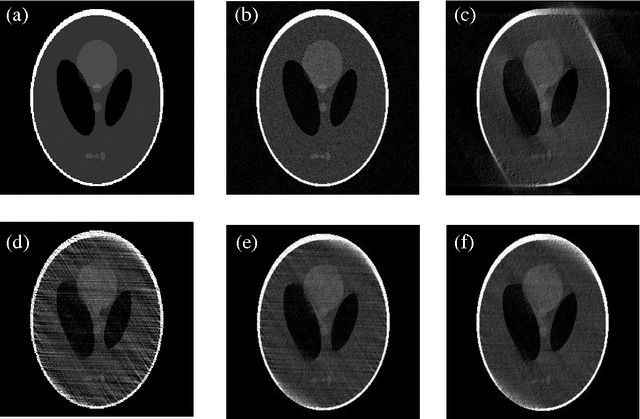

Abstract:In application of tomography imaging, limited-angle problem is a quite practical and important issue. In this paper, an iterative reprojection-reconstruction (IRR) algorithm using a modified Papoulis-Gerchberg (PG) iterative scheme is developed for reconstruction from limited-angle projections which contain noise. The proposed algorithm has two iterative update processes, one is the extrapolation of unknown data, and the other is the modification of the known noisy observation data. And the algorithm introduces scaling factors to control the two processes, respectively. The convergence of the algorithm is guaranteed, and the method of choosing the scaling factors is given with energy constraints. The simulation result demonstrates our conclusions and indicates that the algorithm proposed in this paper can obviously improve the reconstruction quality.